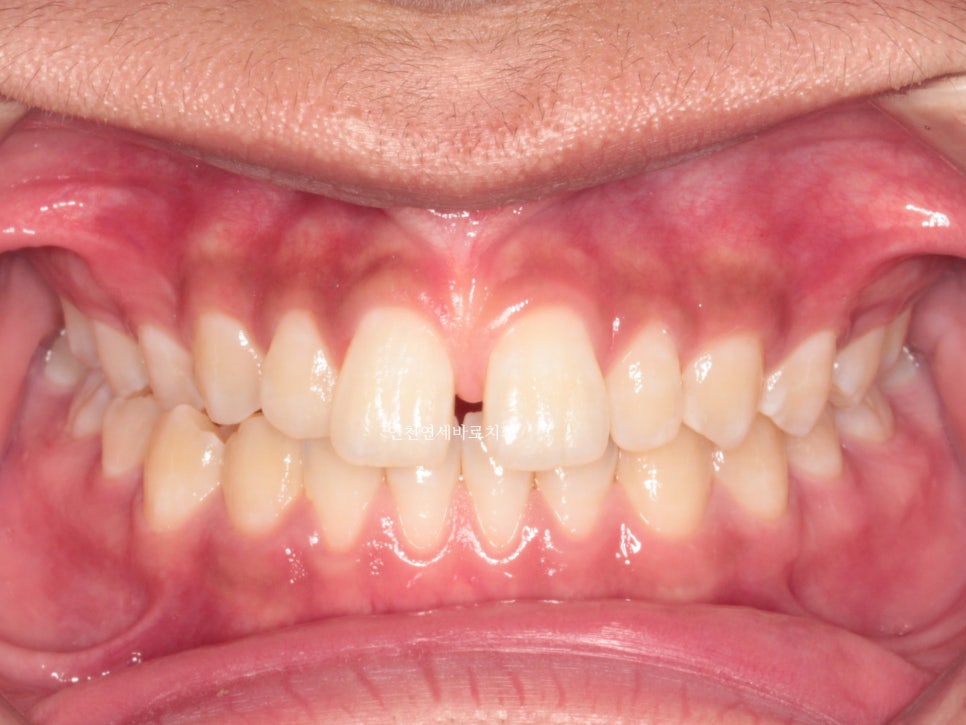

한번의 재제작을 했던 환자분입니다.

재제작 소요기간 한달을 포함해서 환자분이 병원에 오고 딱 1년만에 치료가 마무리 되었습니다.

문제가 되었던 오른쪽 어금니 교합도 좋게 마무리 하였습니다.

악궁확장장치는 사용하지 않았습니다.